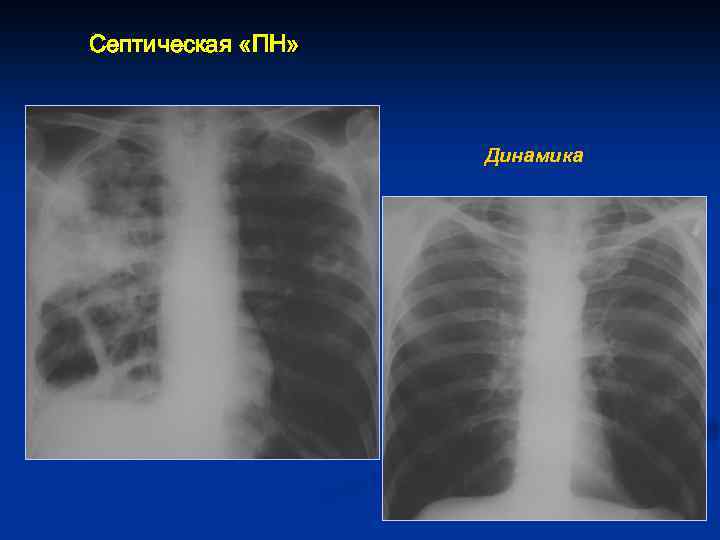

Септическая «ПН» Динамика